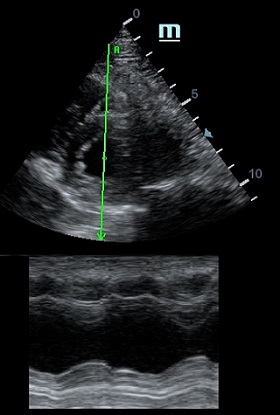

Но как же провести стандартные измерения в М-режиме, если мы его не использовали? На помощь приходит функция Free Xros M – анатомический М-режим. Имея записанную в память прибора видео петлю, мы можем провести линию М-режима в любом месте, при этом корректируя изначально не оптимальный угол.

Возможности применения функции многогранны: от измерения толщины стенок левого желудочка, движения створок митрального клапана и кооптации нижней полой вены до оценки сократимости миокарда как глобально, так и по сегментам.

Показатели УЗ сканирования в М-режиме

Какие показатели можно использовать при анатомическом М-режиме помимо привычных срезов через конец створок митрального клапана или синуса Вальсальве?

Оценка сокращения сегментов левого желудочка на глаз постепенно уходит в прошлое. Если в приборе нет функции радиального или лонгитудинального стрейна, на помощь опять может прийти Free Xros. Утолщение более 5 мм в систолу – нормальное сокращение, 2-5 мм гипокинез, истончение в систолу – дискинез.